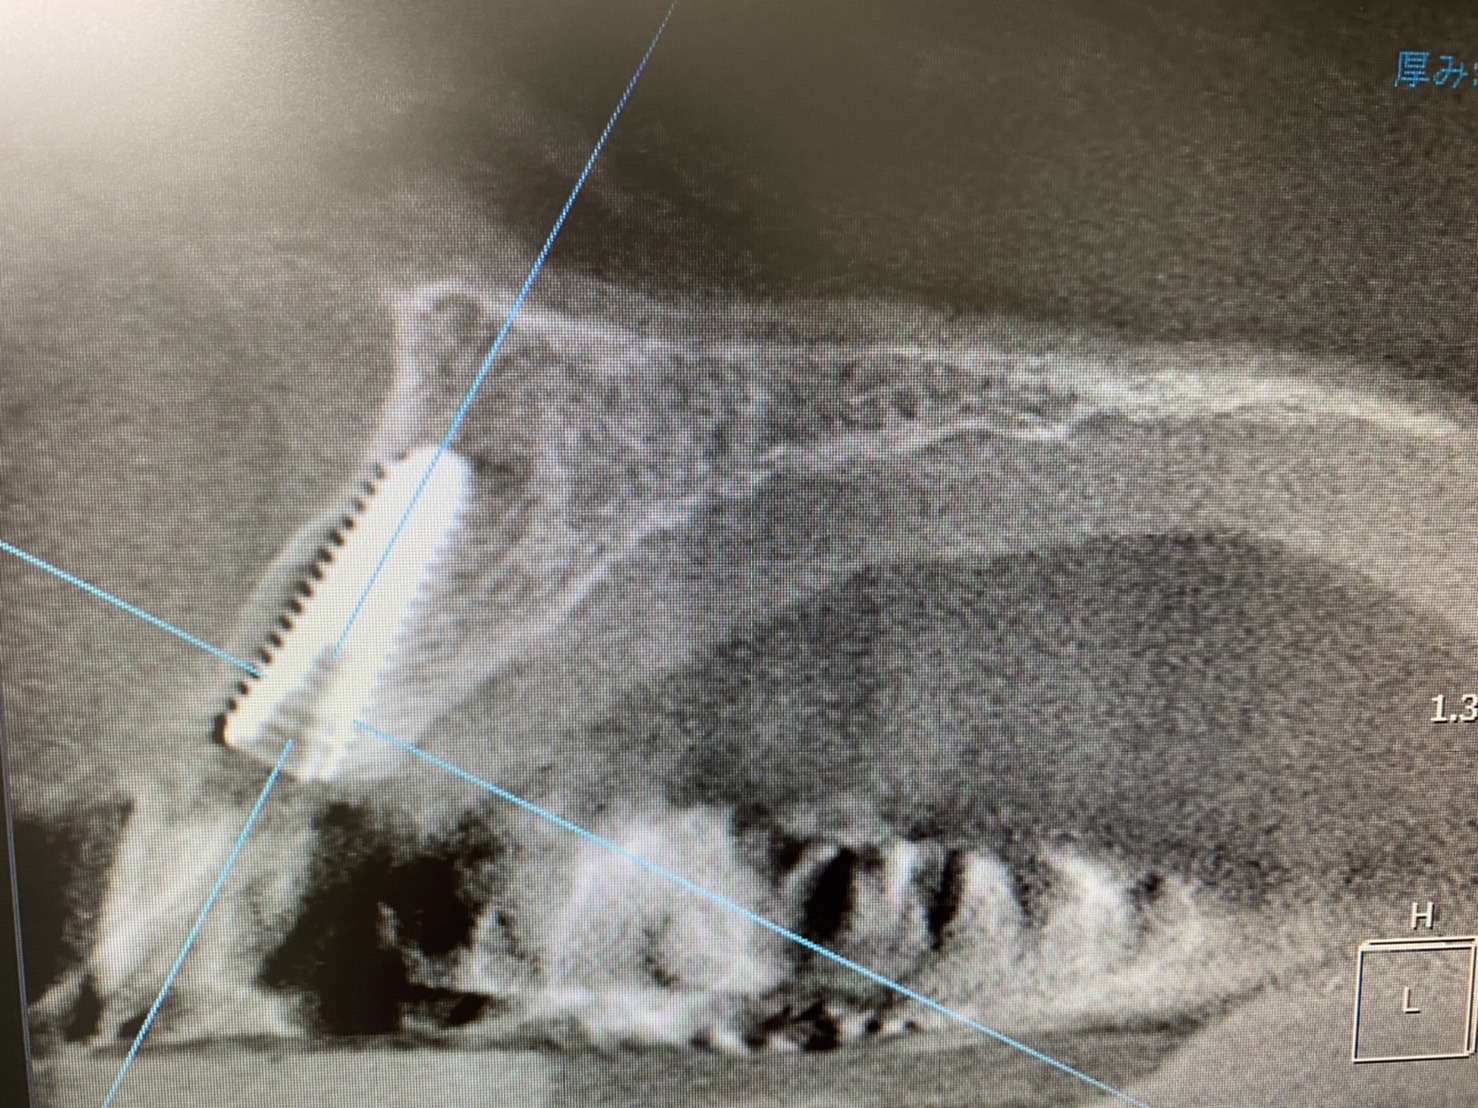

今朝は朝イチより、前歯の抜歯即時埋入、即時荷重

初めは、ソケットシールドの予定でしたが、破折片がかなり動揺してる為に、全て抜歯。

しかし、判断値の2項目も良く

即日荷重まで!

事前にフィクスチャーはワンサイズ大きめ選択し、またドリリングも圧縮拡大をオペ事前から狙っていました。